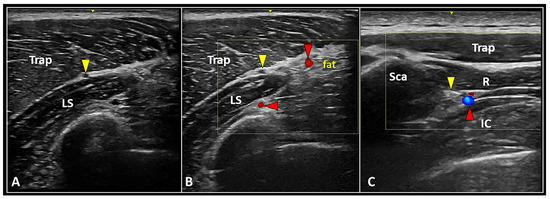

3.4.2. Interfascial Plane Block

- Herbst, M.K.; Sorkin, R. Ultrasound-guided spinal accessory nerve block for intractable trapezius pain. Am. J. Emerg. Med. 2022, 52, 268.e3–268.e7. [Google Scholar] [CrossRef]

- Sultan, H.E.; Younis El-Tantawi, G.A. Role of dorsal scapular nerve entrapment in unilateral interscapular pain. Arch. Phys. Med. Rehabil. 2013, 94, 1118–1125. [Google Scholar] [CrossRef]

- Chang, K.V.; Lin, C.P.; Lin, C.S.; Wu, W.T.; Karmakar, M.K.; Özçakar, L. Sonographic tracking of trunk nerves: Essential for ultrasound-guided pain management and research. J. Pain Res. 2017, 10, 79–88. [Google Scholar] [CrossRef] [PubMed]

| Peripheral Nerve (e.g., SAN, DSN) | Interfascial plane block | High-volume distension of the interfascial plane |